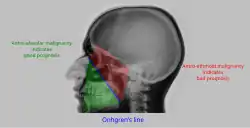

Interpretation of results

| Pathology | Observation |

|---|---|

| None (Normal) |

|

| Maxillary sinusitis[2] | ![]()

| Polyp |

| Malignancy |

![]()